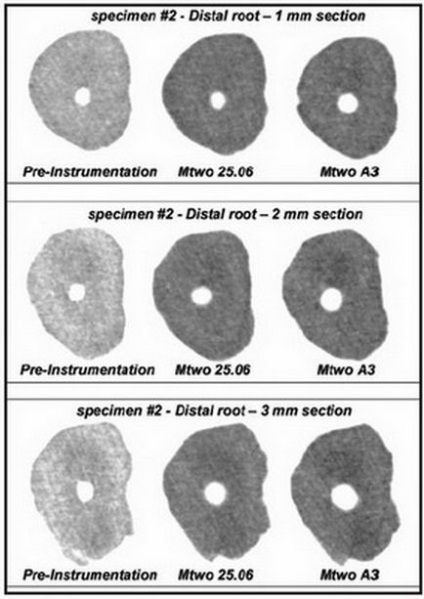

Ábra. 15. keresztmetszete a disztális gyökér az első moláris a maxilla rendre a távolból 1, 2 és 3 mm. a apikális foramen a kezelés és a kezelés után, hagyományos eszközök, Mtwo szekvenciát egy mérete 25 / .06 és használat után Mtwo A3.

- 0,20-0,26 mm mandibuláris őrlőfogak

- 0,18-0,25 mm anteroposterior és zadneschechnom bukkális gyökerei felső őrlőfogak

- 0,22-0,29 mm palatinális gyökerei felső őrlőfogak.

A fenti vizsgálatok megerősítik az ésszerűség a következő megközelítések: gyökércsatorna kell bővíteni a parttól 1 mm-re a csúcs, így az apikális foramen átmérője egyenlő 0,25 mm, ami könnyen megvalósítható segítségével file Mtwo A.